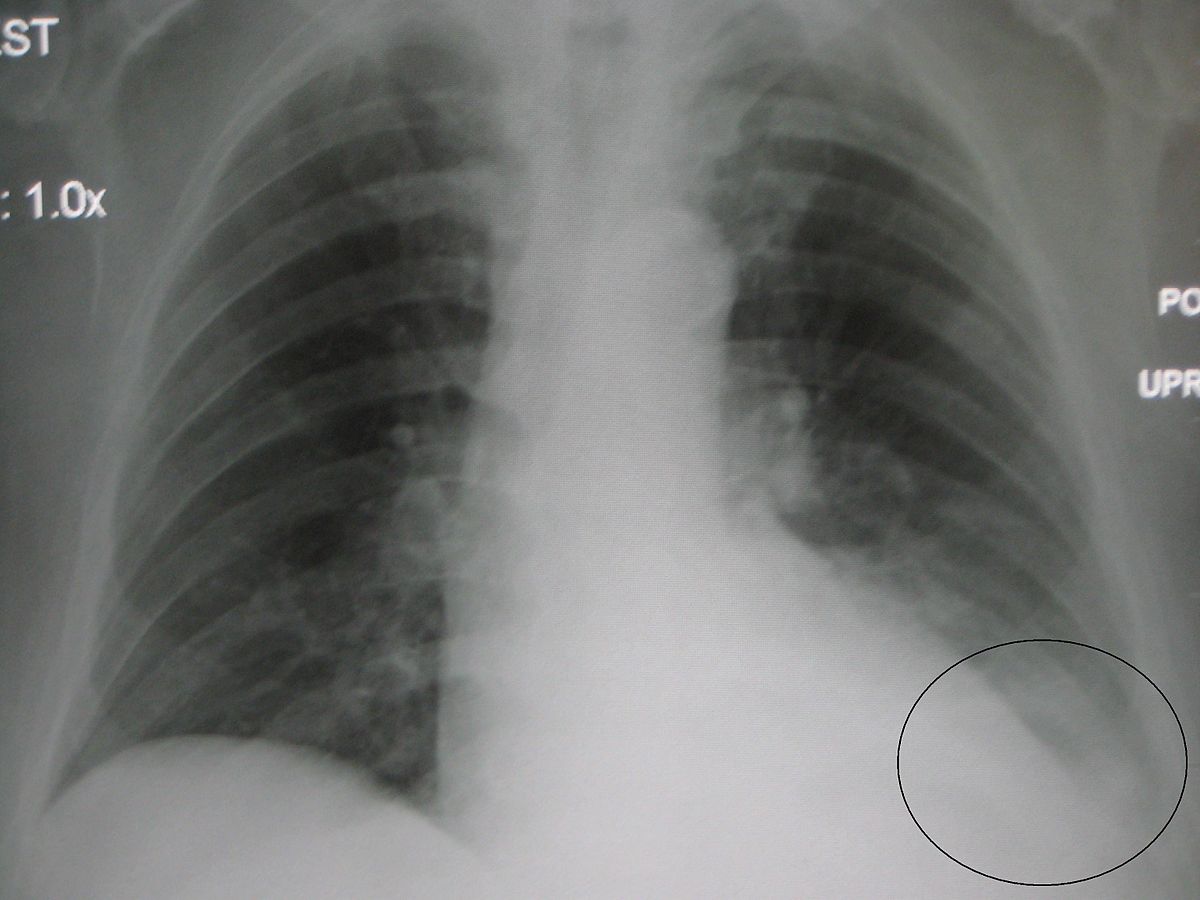

„Megdöbbentő, hogy ez a megelőzhető, kezelhető és könnyen diagnosztizálható betegség még mindig az egyik leggyakoribb halálok a csecsemők és kisgyerekek körében” – mondta Seth Berkley, a Globális Oltóanyag és Oltási Szövetség (GAVI) vezetője. A tüdőgyulladás (pneumonia) a tüdő és a légzőrendszer betegsége, amelyet baktérium, vírus vagy gomba okozhat. A beteg levegőért küzd, miközben tüdejét genny és folyadék tölti meg. Megelőzhető oltással, kezelhető antibiotikumokkal, súlyos esetben oxigénnel, ezek azonban a szegényebb országokban korlátozottan állnak rendelkezésre.